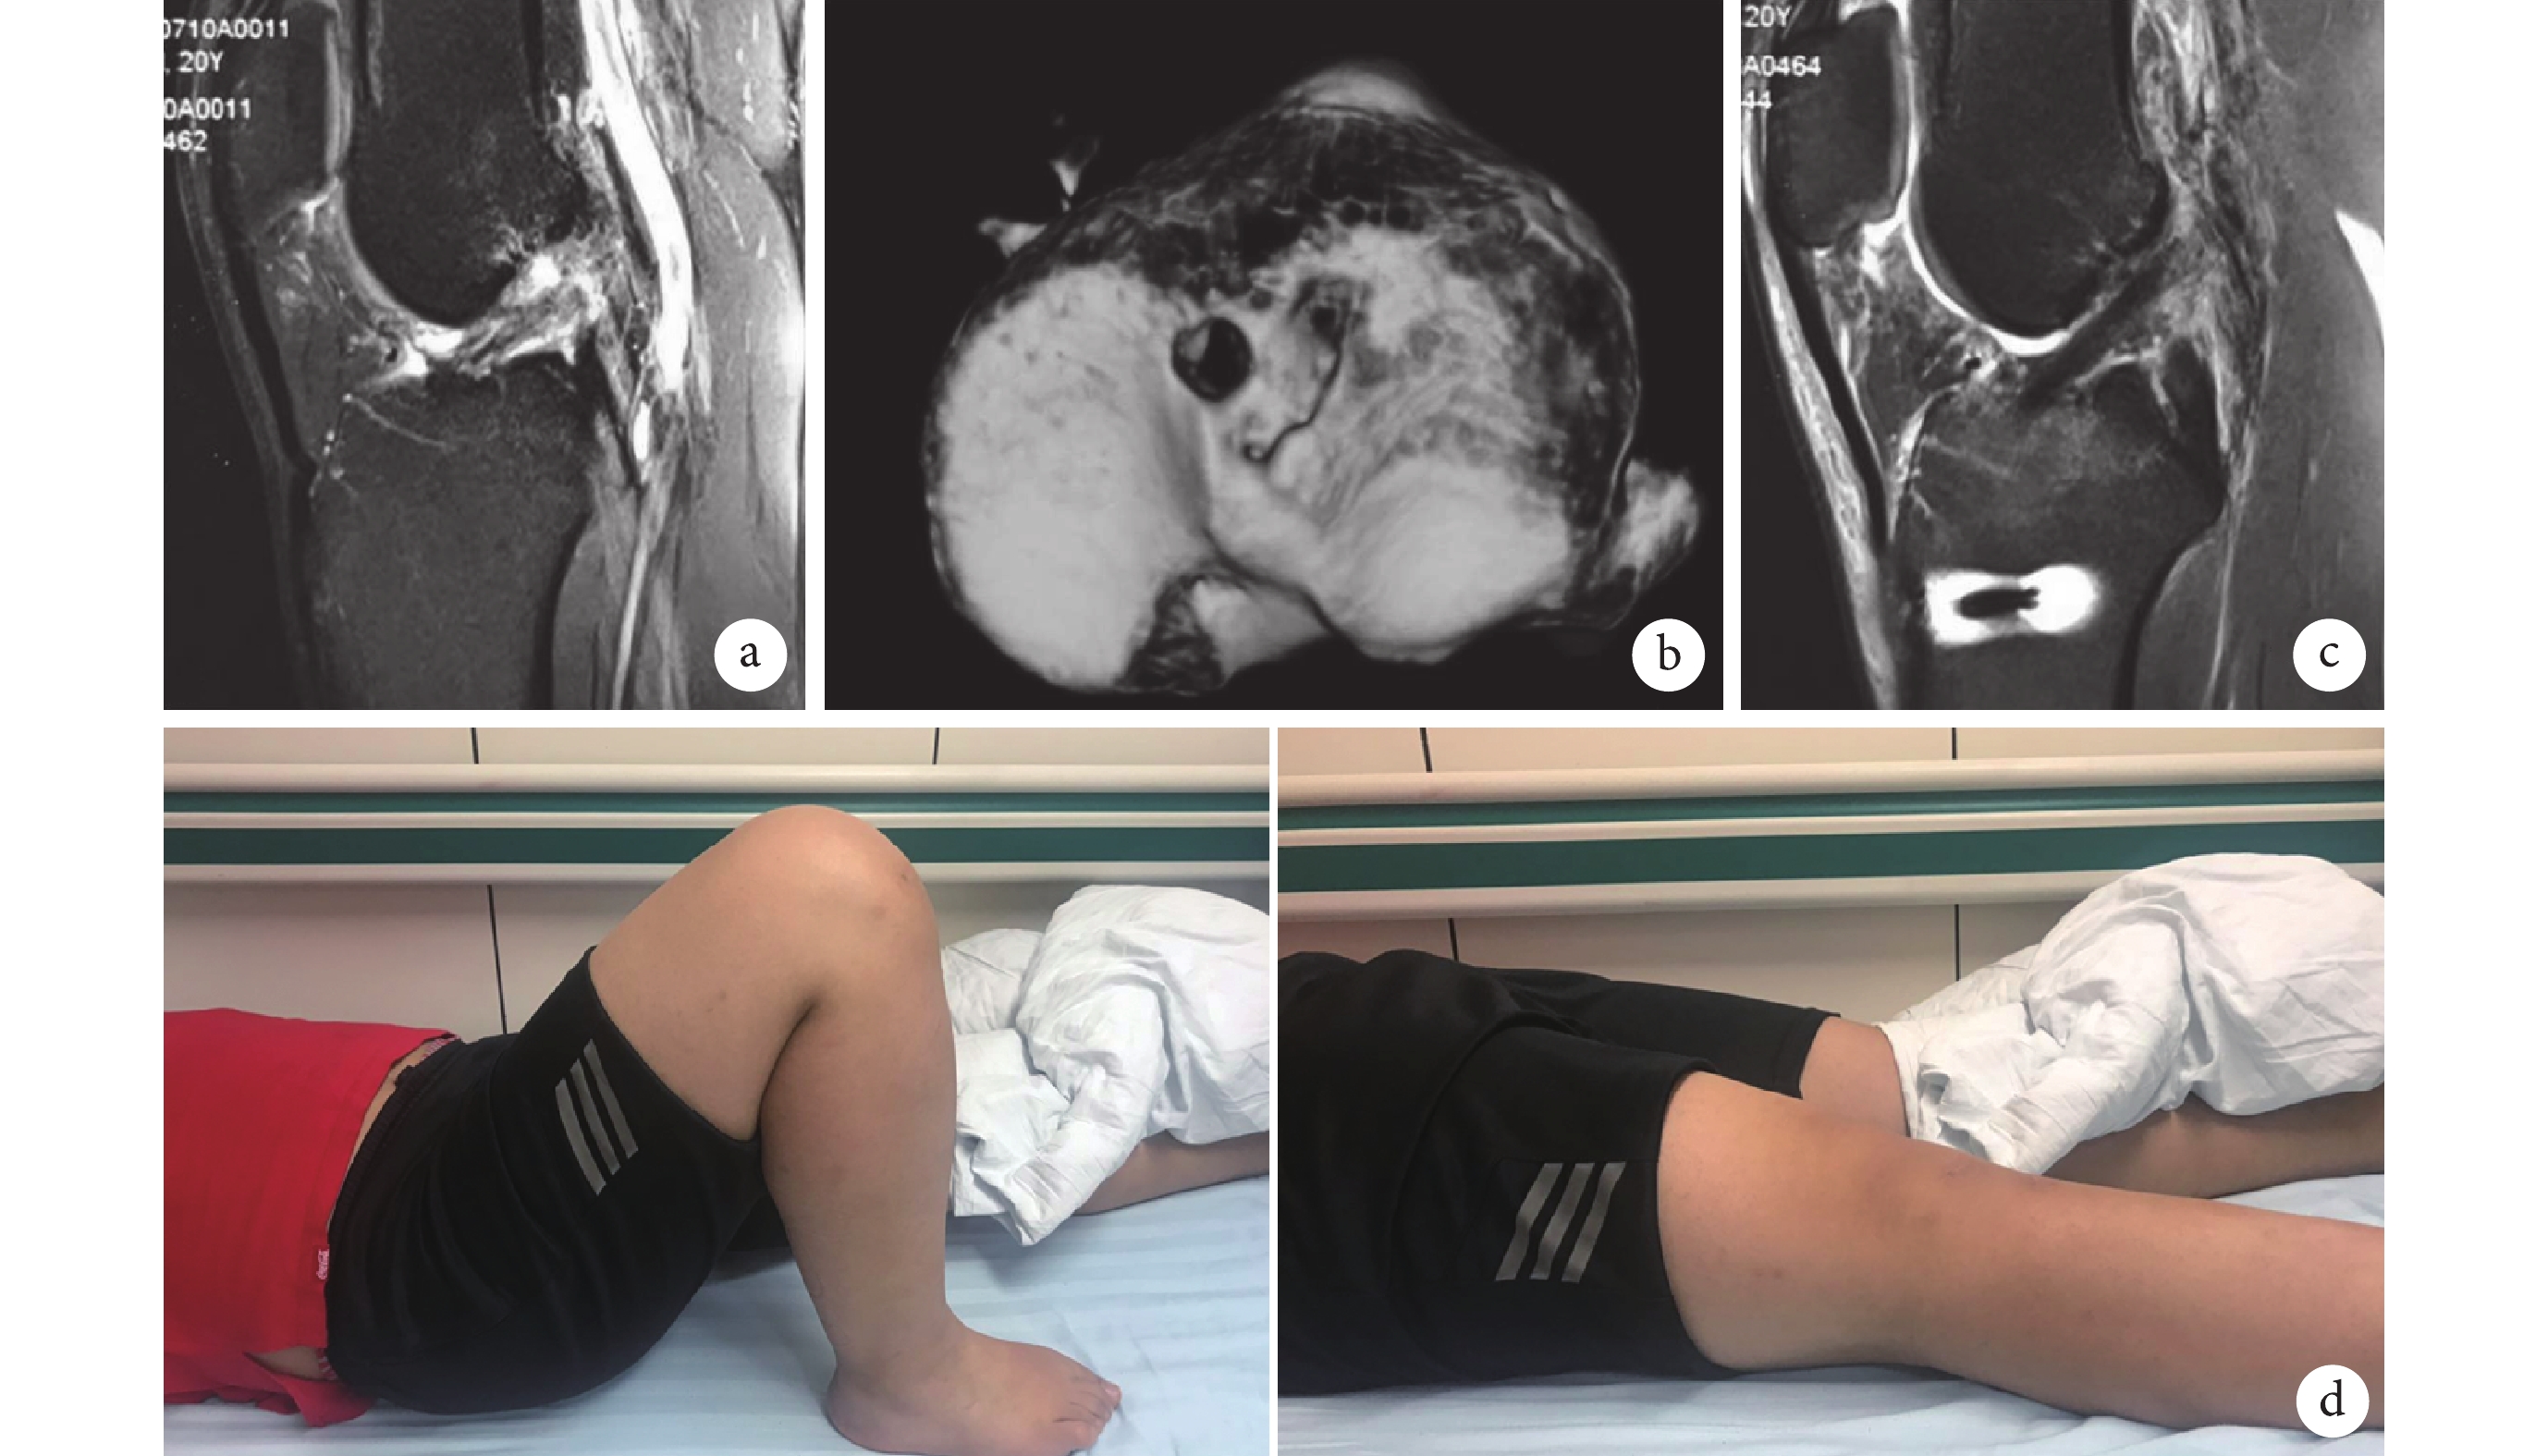

本組術后切口均Ⅰ期愈合,無感染、血腫等并發癥發生。45 例均獲隨訪,隨訪時間 14~32 個月,平均 18.7 個月。術后 3 d 三維 CT 測量脛骨骨道中心點位于矢狀面脛骨平臺前后徑 36.81%~43.35% 處,平均 39.43%;冠狀面上脛骨骨道內緣位于脛骨內側髁間隆起外側。MRI 提示重建 ACL 走行良好(圖2)。

a. 術前 MRI 示 ACL 斷裂;b. 術后 3 d 三維 CT 示骨道位置;c. 術后 3 d MRI 示 ACL 走行接近正常,信號均勻;d. 術后 2 年膝關節屈伸功能

Figure2. A 20-year-old male patient with ACL rupture of the right kneea. Preoperative MRI, showing ACL rupture; b. Three-dimensional CT at 3 days after operation, showing internal site of the tibial tunnel; c. MRI at 3 days after operation, showing nearly normal trend and uniform signal of ACL; d. Flexion and extention of the knee at 2 years after operation